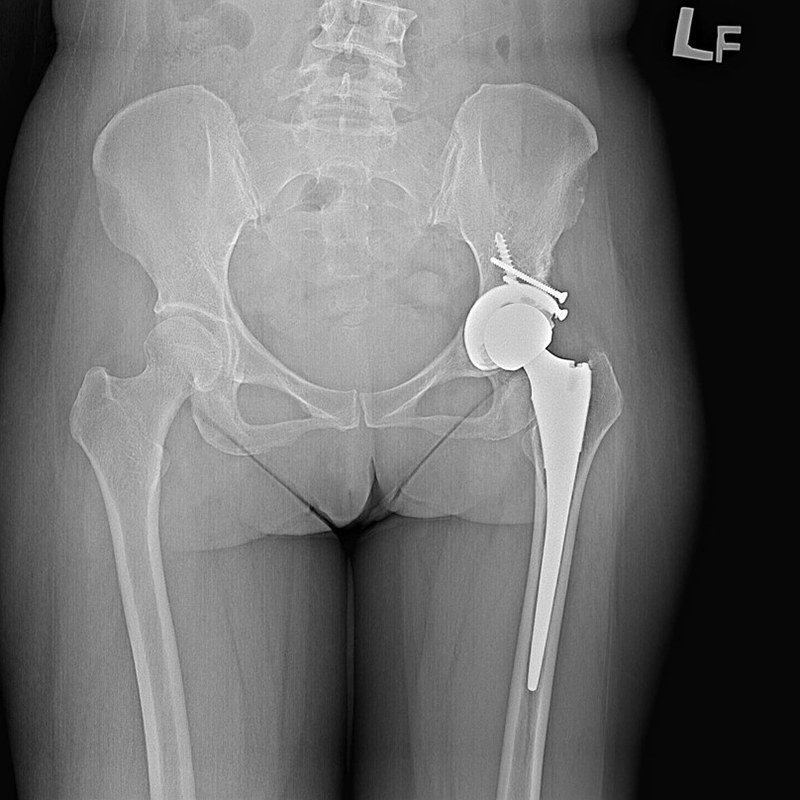

傳統髖關節置換 首頁 案例分享 髖關節手術 傳統髖關節置換 54歲蔡先生退化性關節炎 術前 術後 張女士 51歲 退化性關節炎(DDH先天發育不全 CROWE TYPE 2) 術前 術後 38歲林先生 退化性關節炎 術前 術後 72歲謝女士 退化性關節炎 術前 術後 71歲 謬女士 骨股頭壞死 術前 術後 50歲 郭先生骨股頭壞死 術前 術後 80歲 盧先生骨股頭壞死 術前 術後 林先生 37歲 術前 術後 邱女士 51歲 術前 術後 張女士 50歲 術前 術後